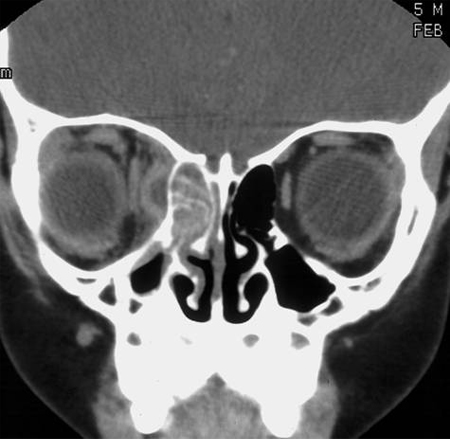

CT სკანირება კონტრასტით არის არჩევითი ვიზუალიზაციის კვლევა მწვავე რინოსინუსიტის საეჭვო გართულებების შემთხვევაში.[1][22]

მწვავე რინოსინუსინუსიტისთვის დამახასიათებელი, მაგრამ არა დიაგნოსტიკური, ნიშნები მოიცავენ სინუსის დაჩრდილვას, აირ-სითხის დონეს, ან ლორწოვანი გარსის გამოკვეთილ ან ძლიერ შესქელებას.[1][22]

სინუსების ღრუების მიმოხილვითი რენტგენოგრაფია სხვადასხვა პროექციაში (პირდაპირი, ოქციპიტო-მენტალური, გვერდითი) სინუსის პუნქციასთან შედარებით ხასიათდება 76%-იანი სენსიტიურობით და 79%-იანი სპეციფიურობით.[1][Figure caption and citation for the preceding image starts]: მარჯვენა ეთმოიდური სინუსის დაჩრდილვა და მოსაზღვრე ორბიტალური აბსცესი კომპიუტერულ ტომოგრამაზეექ. Melissa Pynnonen-ის კოლექციიდან [Citation ends].